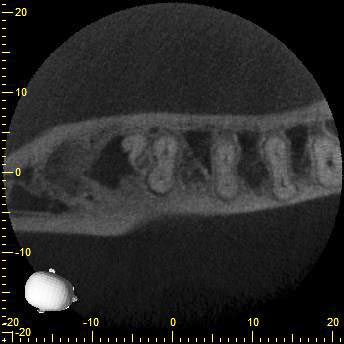

KD47-6

Und das hier war einfach nur Pech…